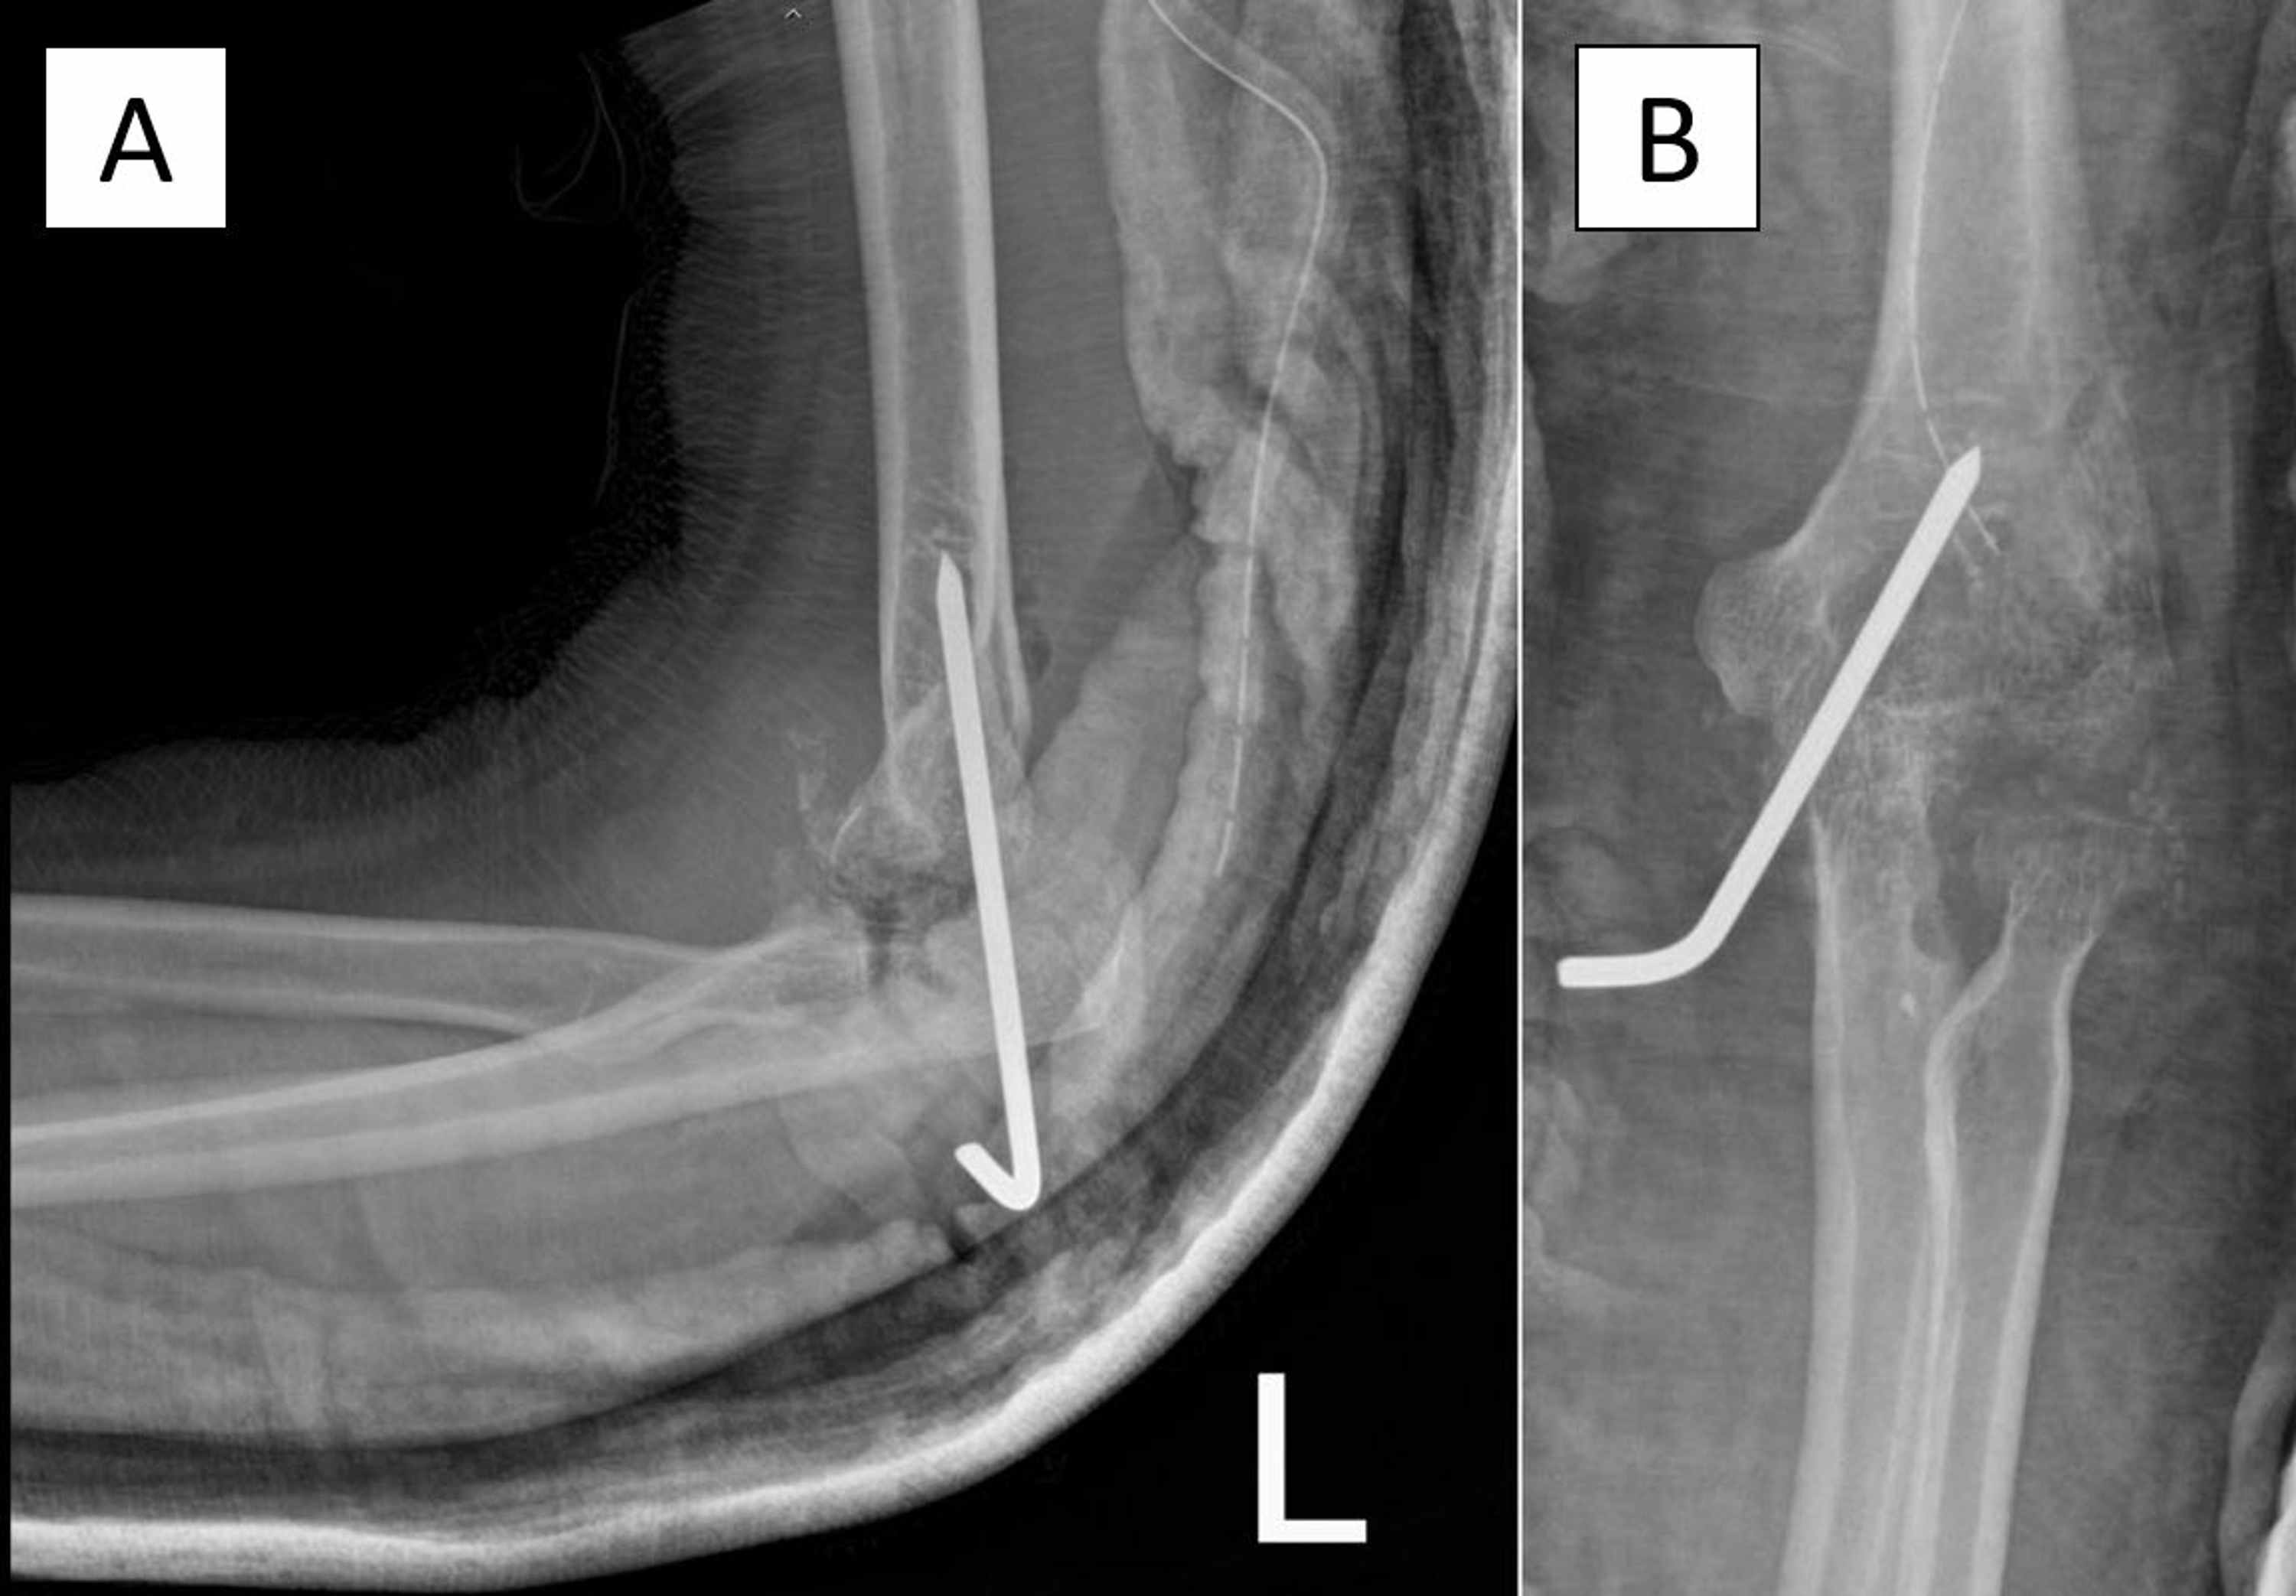

Elbow septic arthritis in children clinical presentation an Septic Arthritis Elbow X Ray Septic arthritis presents with a hot, swollen, acutely painful joint with restriction of movement. Oligoarticular septic arthritis is more likely to present with symptoms of systemic infection and more commonly affects the shoulder, wrist, and. Septic arthritis of the shoulder and elbow primarily affects individuals with clinical comorbidities and/or those who are. The differential diagnosis of an acutely painful joint. Septic Arthritis Elbow X Ray.